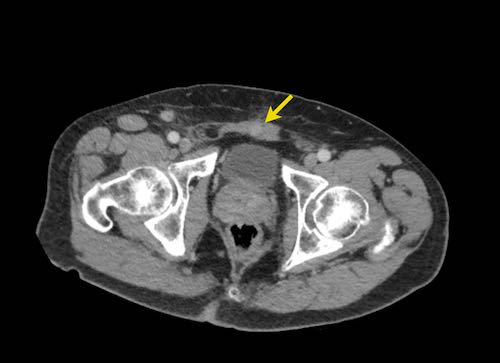

Ở vùng chậu, vị trí quan trọng nhất là túi cùng trực tràng-tử cung và trực tràng-bàng quang (túi cùng Douglas).

Đôi khi có thể thấy di căn khối u lan ra phía trước bàng quang, nhưng không xâm lấn thành bàng quang, do bàng quang là cơ quan nằm ngoài phúc mạc.

Tuy nhiên, vòm bàng quang phía trên và ống niệu rốn được ngăn cách với khoang bụng bởi một lớp phúc mạc thành, tạo thành đích tiềm năng cho các tế bào khối u.

Đặc biệt khi bàng quang đầy, các tổn thương di căn phúc mạc có thể được quan sát thấy ở phía trước bàng quang, áp sát thành bụng trước.

Đây không phải là bệnh lý quanh bàng quang, vì khoang quanh bàng quang nằm ngoài phúc mạc và không thông với khoang trong phúc mạc.